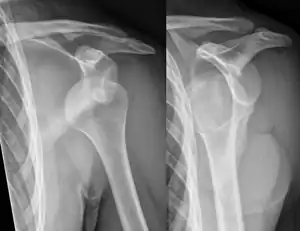

| Anterior dislocation of the left shoulder. | |

An anterior dislocation of the shoulder

Anterior dislocation of the right shoulder. AP X ray